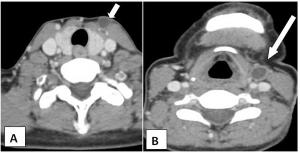

Case History: 75-year-old male presents with complaint of mucus discharge from external opening on skin at anterior aspect of mid part of neck on the left side.